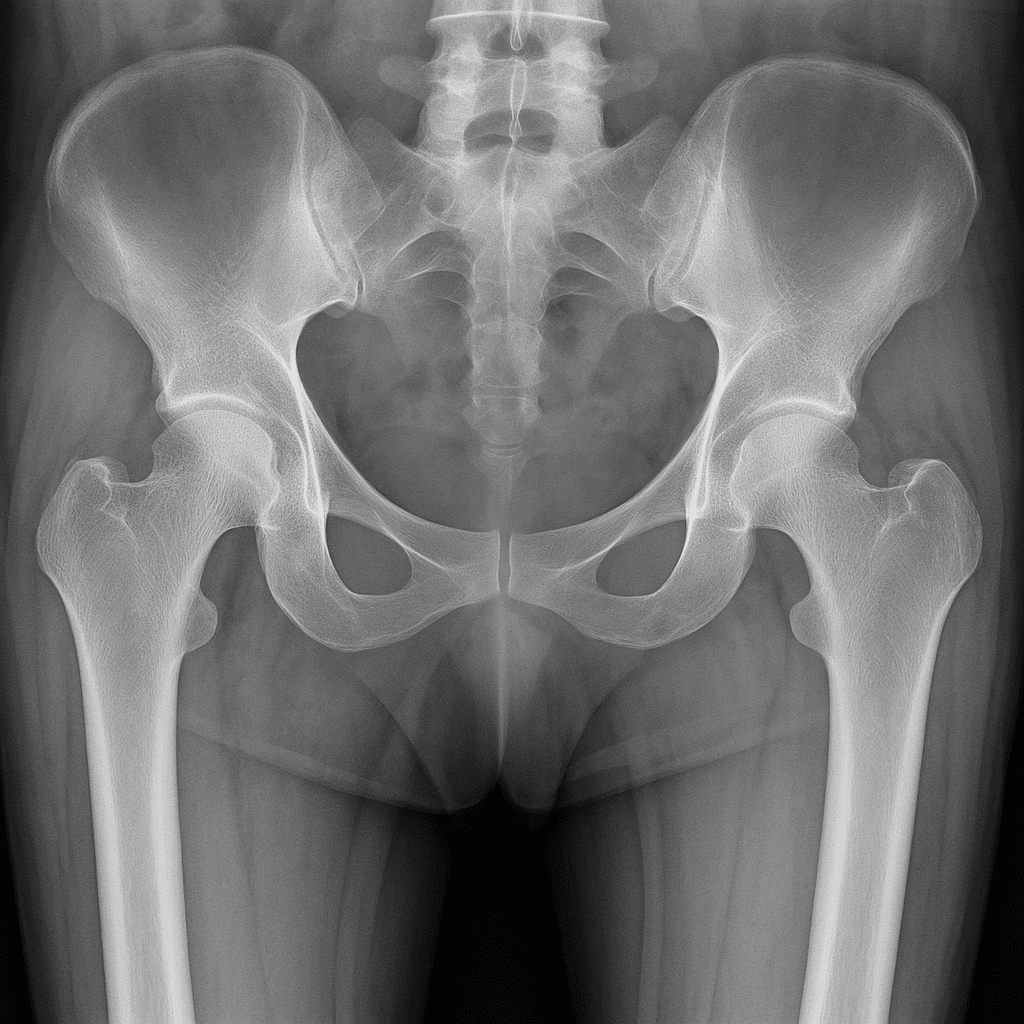

A ‘fragility’ fracture is a broken bone caused by a fall from a standing height or less. These fractures often affect older adults and are rising sharply, with over half a million cases annually across the UK. These injuries, often resulting from osteoporosis, lead to significant pain, disability, and loss of independence for patients. They also place immense pressure on the NHS, costing an estimated £2.2 billion each year. Therefore, it is important that we provide the best possible rehabilitation to enable people to return home, and to thrive at home after their fracture.

Over a 14-month period, the project – funded by UK Research and Innovation – explores the feasibility of using clinical natural language processing (NLP) to analyse rehabilitation from thousands of electronic health records (EHRs) from patients treated for hip, leg, and ankle fractures at Barts Health NHS Trust. The NLP will be used to ideally identify which approaches led to the best outcomes for patients.